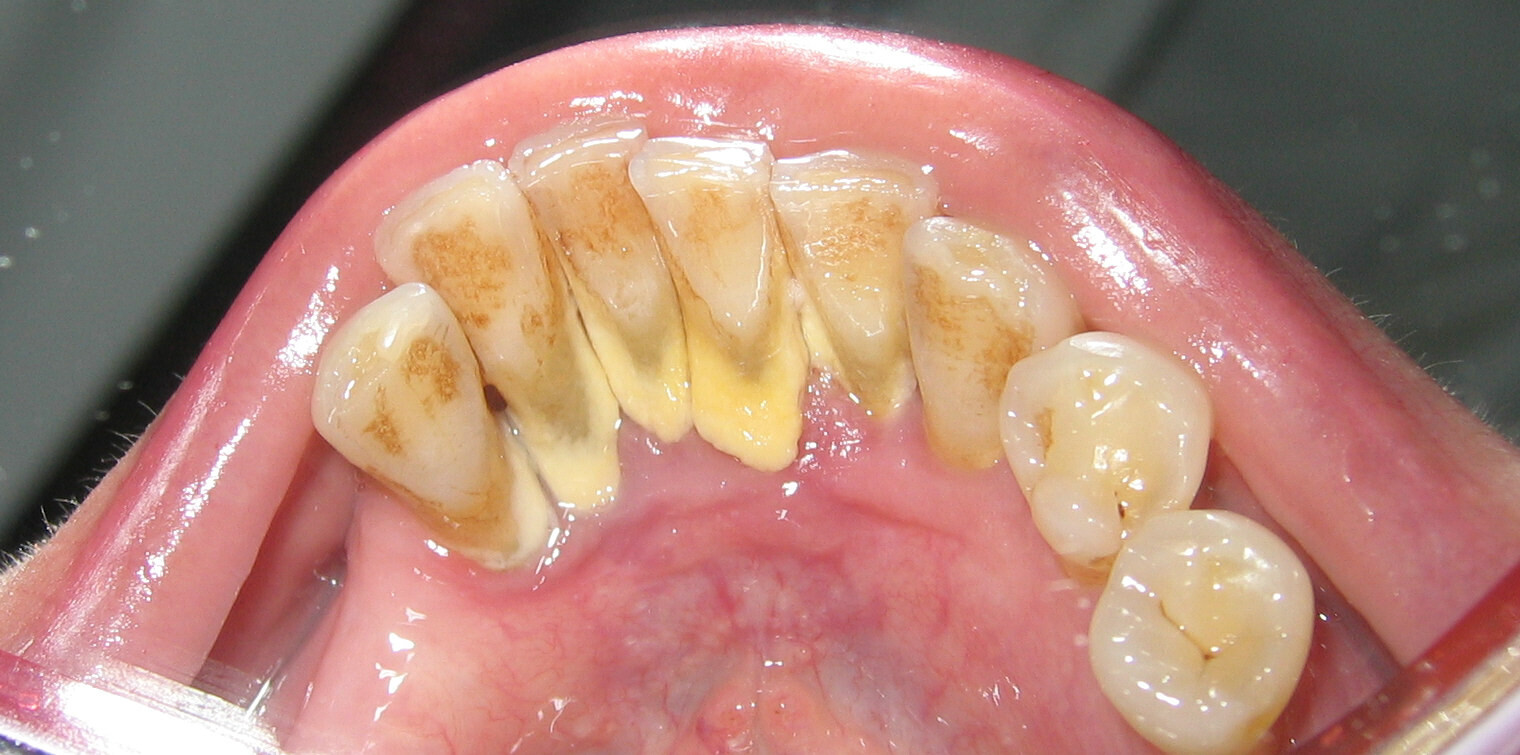

According to the IJDHS review, there are two types of dental calculus: supragingival and subgingival. The difference between the two types is the location of the calculus relative to the edge of the gum tissue.

If you think of the edge of the gums like a shirt sleeve and imagine the tooth is like your hand in the sleeve, you can get a better image of this classification. The parts of your hand and wrist that extend visibly outside the sleeve would be considered supragingival (above the gumline), whereas anything unseen below the sleeve would be considered subgingival (below the gumline). Calculus above the gumline can appear whitish or yellowish in color.

Removing Supragingival Calculus